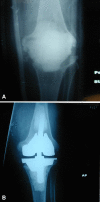

Background: The best method for managing large bone defects during revision knee arthroplasty is unknown. Metaphyseal fixation using porous tantalum cones has been proposed for severe bone loss. Whether this approach achieves osseointegration with low complication rates is unclear.

Methods: We retrospectively reviewed 27 patients who had 33 tantalum cones (nine femoral, 24 tibial) implanted during 27 revision knee arthroplasties. There were 14 women and 13 men with a mean age of 64.6 years. Preoperative diagnosis was reimplantation for infection in 13 knees, aseptic loosening in 10, and wear-osteolysis in four. Patients were evaluated clinically and radiographically using the score systems of the Knee Society and followed for a minimum of 2 years (mean, 3.3 years; range, 2-5.7 years).

Results: One knee with two cones was removed for infection. All but one cone showed osseointegration. One knee was revised for femoral cone and component loosening. There was one reoperation for femoral shaft fracture and one for superficial dehiscence. The mean Knee Society pain score improved from 40 points preoperatively to 79 points postoperatively. The mean function score improved from 19 points to 47 points.

Conclusions: Our observations suggest metaphyseal fixation with tantalum cones can be achieved. Longer-term followup is required to determine whether the fixation is durable.